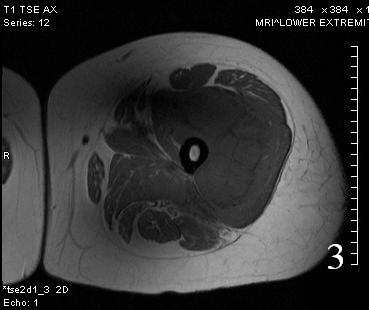

GENERAL INFORMATION Tumoral calcinosis is a very rare entity, characterized by large tumorlike calcium deposits and painless mass, arising near to the articular soft tissue areas. Common areas affected are elbows, hips, knees rarely involve hands and feet. No obvious...